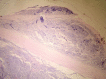

Orbital retinoblastoma is a catastrophic event traditionally carrying a dismal prognosis. Although its incidence is less in the developed countries it continues to be one of the major diagnosis at presentation in the developing world. Orbital retinoblastoma encompasses a wide range of distinct clinical entities with varying tumor load. There are no standard treatment protocols as of now but the current preferred management is multimodal with a combination of initial high-dose chemotherapy, surgery, external beam radiotherapy and prolonged chemotherapy for twelve cycles. In spite of progress on all fronts including surgical, medical, diagnostic, genetic and rehabilitative with improving survival rates, however, lack of access to medical facilities, lack of education about the need for early medical attention and cultural resistance to enucleation continue to contribute to an epidemic of extra ocular disease at diagnosis in the developing world. This review introduces the various terminologies used in the spectrum of orbital retinoblastoma, discusses in details the clinical aspects and management protocols, current status and the future directions.